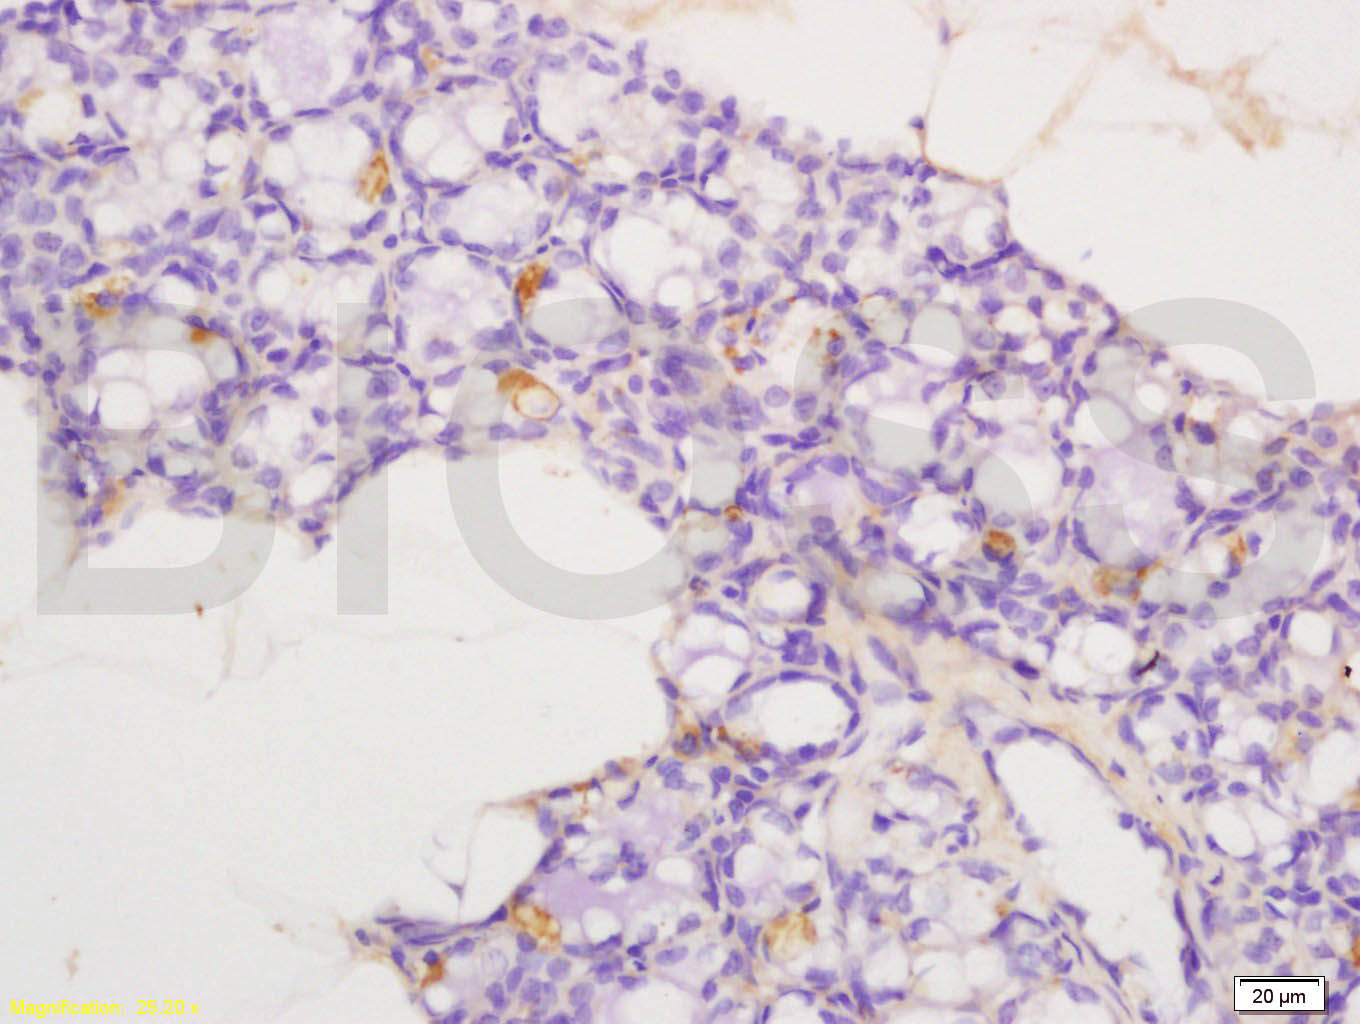

Tissue/cell: rat exfoliated cells; 4% Paraformaldehyde-fixed and paraffin-embedded; Antigen retrieval: citrate buffer ( 0.01M, pH 6.0 ), Boiling bathing for 15min; Block endogenous peroxidase by 3% Hydrogen peroxide for 30min; Blocking buffer (normal goat serum,C-0005) at 37℃ for 20 min; Incubation: Anti-MIP-1 Beta Polyclonal Antibody, Unconjugated(bs-1046R) 1:200, overnight at 4°C, followed by conjugation to the secondary antibody(SP-0023) and DAB(C-0010) staining